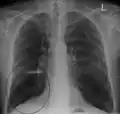

A chest X-ray is not useful to establish a diagnosis of COPD but it is of use in either excluding other conditions or including comorbidities such as pulmonary fibrosis and bronchiectasis. Characteristic signs of COPD on X-ray include hyperinflation (shown by a flattened diaphragm and an increased retrosternal air space) and lung hyperlucency.[5] A saber-sheath trachea may also be shown that is indicative of COPD.[117]

- Chest X-ray demonstrating severe COPD, displaying small heart size in comparison to the lungs